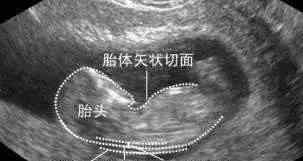

NT实际上是对颈部后方半透明区厚度的检查,这是胎儿颈椎在水平变形切面上的皮肤与皮下软组织之间的最大厚度。这里需要的是正位移,也就是孩子的鼻子和嘴巴朝上,侧脸对着镜头的位置。